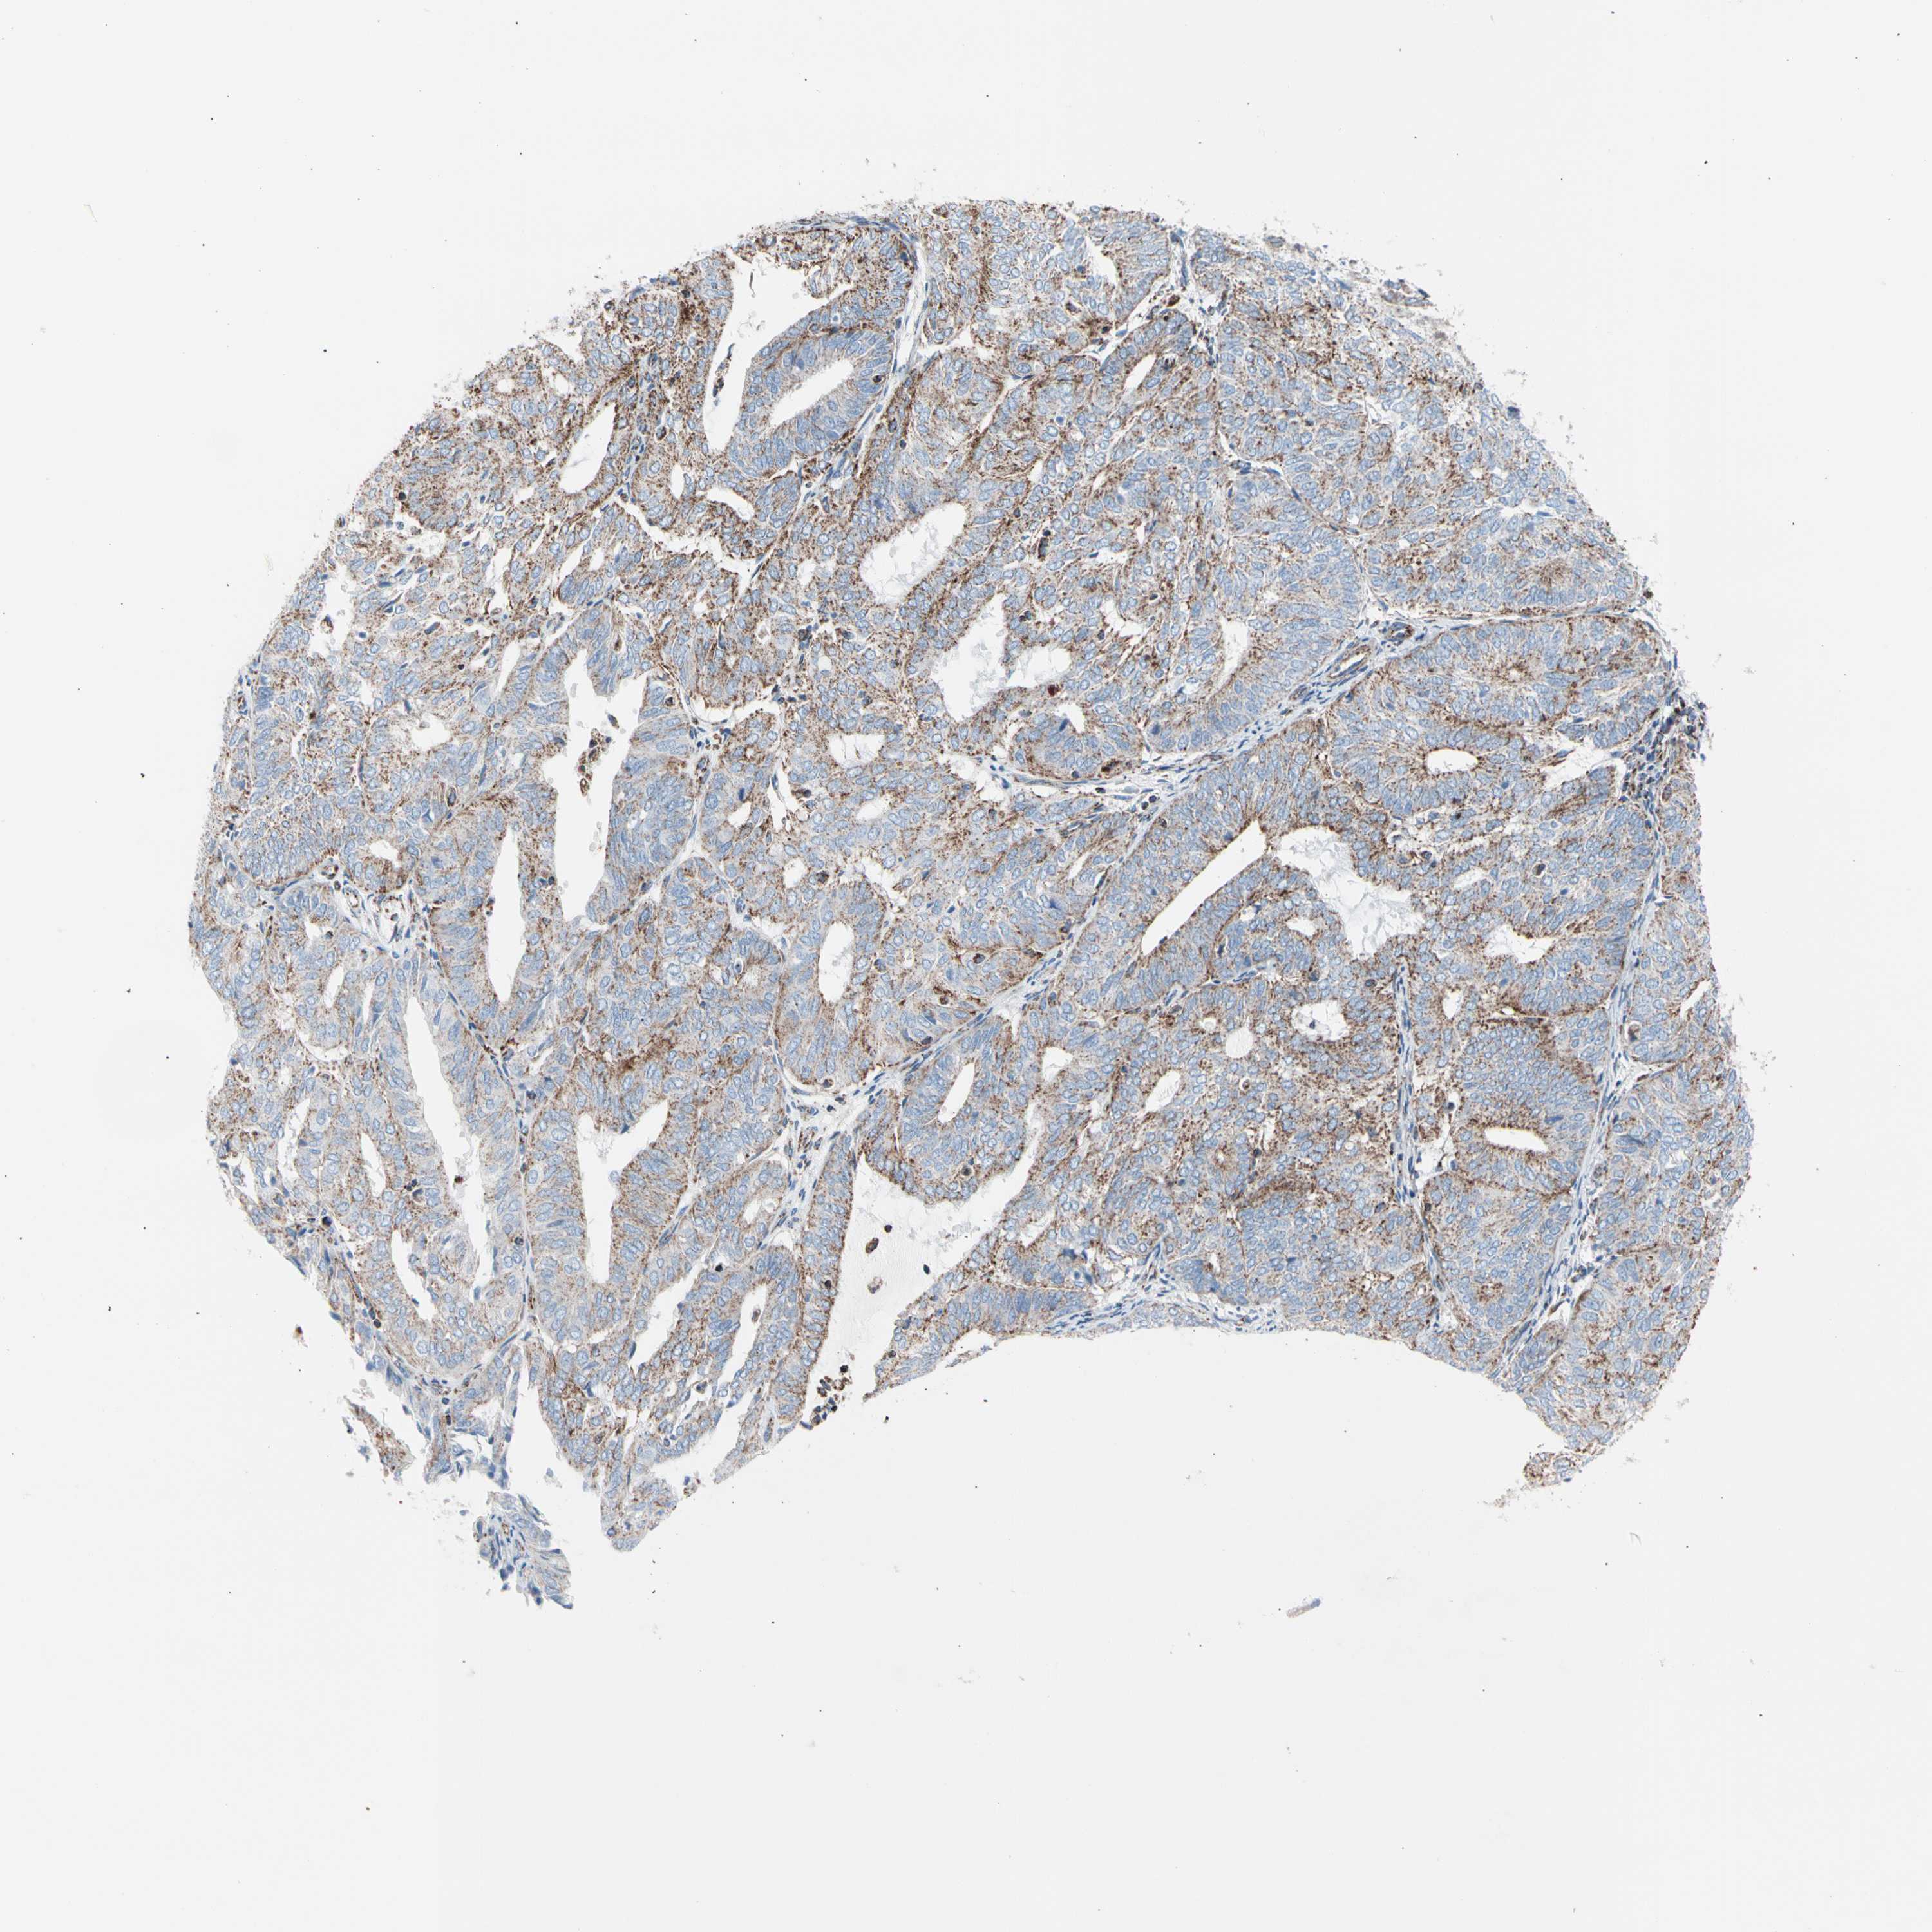

ENDOMETRIAL CANCER - Protein expressioni

A mouse-over function shows sample information and annotation data. Click on an image to view it in a full screen mode. Samples can be filtered based on level of antibody staining by selecting one or several of the following categories: high, medium, low and not detected. The assay and annotation is described here.

Note that samples used for immunohistochemistry by the Human Protein Atlas do not correspond to samples in the TCGA dataset.

Antibody stainingi

Antibody staining in the annotated cell types in the current human tissue is reported as not detected, low, medium, or high, based on conventional immunohistochemistry profiling in selected tissues. This score is based on the combination of the staining intensity and fraction of stained cells.

Each image is clickable and will lead to virtual microscopy that enables deeper exploration of all samples and also displays staining intensity scores, fraction scores and subcellular localization as well as patient and tissue information for each sample.

Antibody HPA007043

Antibody HPA007044

Antibody CAB010052

Staining

High

Medium

Low

Not detected

Intensity

Strong

Moderate

Weak

Negative

Quantity

>75%

75%-25%

<25%

None

Location

Nuclear

Cytoplasmic/membranous

Cytoplasmic/membranous,nuclear

Adenocarcinoma, NOS